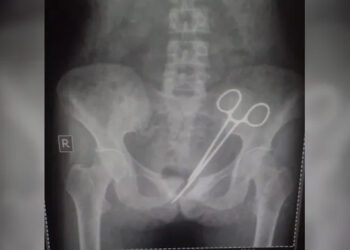

പ്രസവ ശസ്ത്രക്രിയയ്ക്ക് പിന്നാലെ നവജാതശിശു മരിച്ചു; കായംകുളത്തെ സ്വകാര്യ ആശുപത്രിയിൽ ചികിത്സാ പിഴവെന്ന് പരാതി

ആലപ്പുഴ: ചികിത്സപിഴവിനെ തുടർന്ന് നവജാതശിശു മരിച്ചതായി പരാതി. കായംകുളം മെഡിക്കൽ ട്രസ്റ്റ് ആശുപത്രിക്ക് എതിരെയാണ് പരാതി ഭരണിക്കാവ് സ്വദേശികളായ അതുല്യ - അജീഷ് ദമ്പതികളുടെ കുട്ടിയാണ് മരിച്ചത്. ...